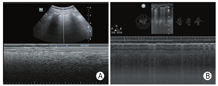

沙滩征:M型模式扫查,可见由胸膜线上方波浪线样的线性高回声与胸膜线下方由肺滑动产生的均匀颗粒样点状回声共同形成类似沙滩样表现的超声影像(图5)。

横向扫查时,显示光滑胸膜线,至少显示2条水平方向的A线;纵向扫查时表现为"蝙蝠征"(两侧肋骨声影与之间胸膜线构成)。正常肺部图像应显示胸膜线、A线,能够观察到肺滑动征(图4)。

胸膜线:胸膜与肺表面界面声阻抗差异形成的回声反射,呈光滑、清晰、规则的线性高回声。

A线:胸膜与肺界面声阻抗的差异产生多重反射而形成的伪像,位于胸膜线下方,呈一系列与之平行的光滑、清晰、规则的线性高回声,彼此间距相等,回声由浅入深逐渐减弱至消失。

肺滑动征:实时超声下可见脏层胸膜与壁层胸膜随呼吸运动而产生一种水平方向的相对滑动。